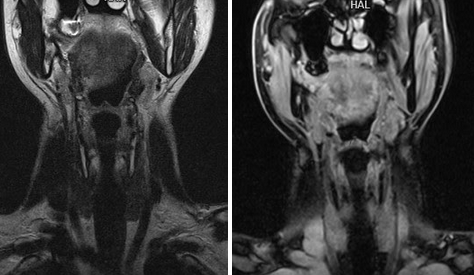

(Слева) КТ с КУ, сагиттальная проекция. Девушка с образованием в области корня языка. Срединное плотное образование, расположенное в области корня языка, вероятнее всею является эктопированной щитовидной железой. Дополнительная эктопированная ткань лежит кпереди от подъязычной кости.

(Справа) КТ с КУ у пациента с язычной щитовидной железой, аксиальная проекция. На уровне щитовидною хряща железа не определяется.

(Слева) КТ с КУ, аксиальная проекция. Подслизистое образование с четкими контурами, расположенное вдоль средней линии дна полости рта. Неоднородная плотность говорит о возникновении зоба.

(Справа) При МРТ Т1ВИ в сагиттальной проекции определяется неоднородное гиперинтенсивное образование, расположенное вдоль средней линии корня языка. Обратите внимание на сужение просвета ротоглотки, а также смещение надгортанника кзади и книзу.